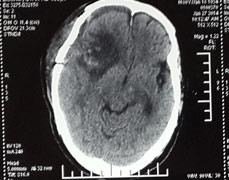

日前我院神经外科成功为一80岁高龄脑瘤患者实施了开颅肿瘤切除术,切除了一个5.6cm×6.3cm×5.7cm的巨大脑膜瘤,并保持了老人术后头颅外观形态...